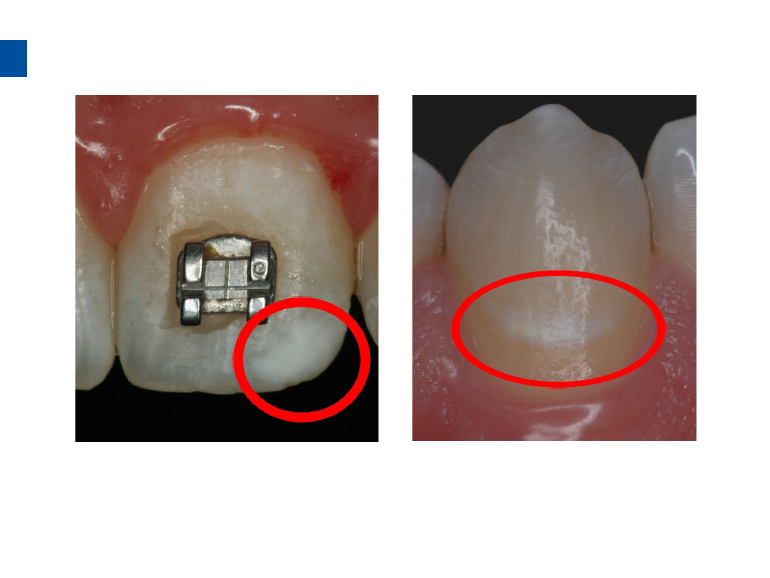

二、爱康渗透树脂唇颊面装Icon Caries Infiltrant – vestibular,治疗唇颊面釉质早期龋。(整个套装包含一次治疗两至三个早期龋损所需的材料。一次性使用,如果邻牙有类似病变可一并治疗)。

1、治疗之前清洁患牙及邻牙,冲洗干净,上橡皮障。避免使用如Flexi Dam之类的热塑性橡胶材质的橡皮障。放置合适的楔子进入牙间隙,将柄部弯曲或折断可以让楔子更好的进入邻面。

3、小心旋转注射器柄部,将足量材料涂布于龋损区域之上,等待2分钟,并用棉球去除多余材料,酸蚀范围应至龋损外2mm处,如果正畸患者托槽取下后发现牙面大范围早期龋损则需酸蚀整个牙面。(单手可完成注射器操作)。

2.酸蚀后的牙釉质表面呈白垩色,如未呈现此颜色则需重复酸蚀。